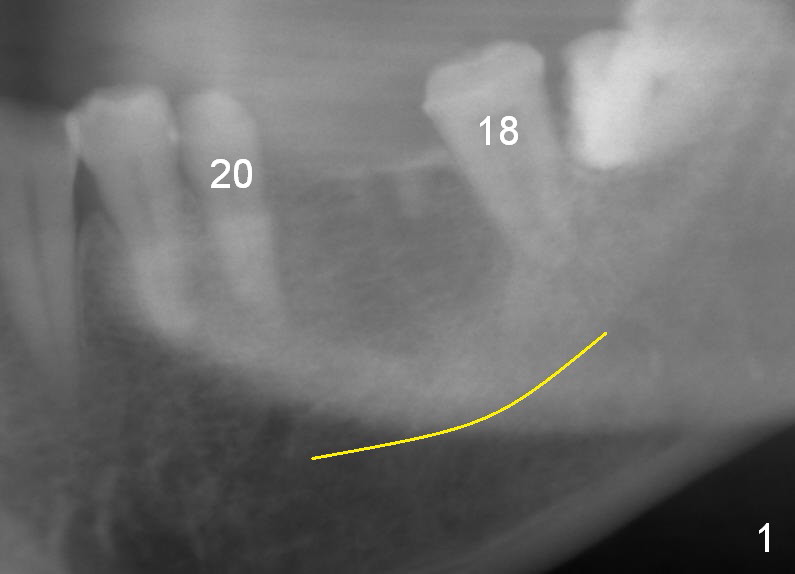

A 49-year-old man cannot quit smoking.  The lower left fixed partial prosthesis (FPD) has been dislodged (Fig.1).  It appears that the patient is a bruxer.  The bone height seems to be unlimited (yellow line in Fig.1,2: the upper border of the Inferior Alveolar Canal).  It should be safe to place a 12 or 14 mm long bone level implant (Fig.2).  The initial osteotomy depth is 12 mm.